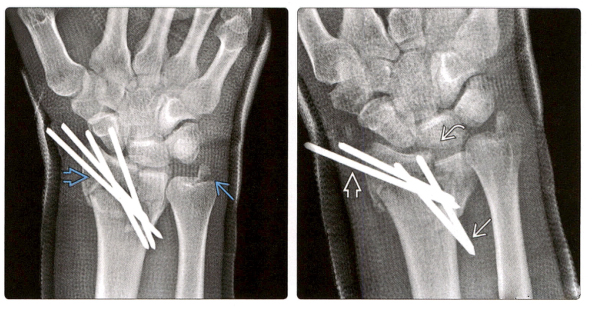

3.(Снимок слева) Задне-передняя рентгенограмма, сделанная сразу после репозиции перелома, показывает, что четыре спицы К пронизывают шиловидный отросток лучевой кости, а фрагменты перелома близки к анатомической репозиции. Дополнительная внешняя фиксация, вспомогательная фиксация.

(Фото справа) Заднепередняя рентгенограмма того же пациента через 2 недели показала смещение спицы К и неспособность редукции перелома, 2 спицы К пролапсировались, а 2 спицы К были смещены проксимально.